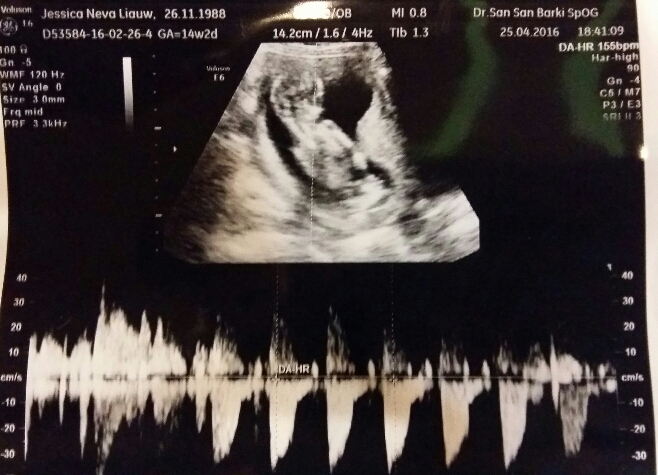

Happy news, my baby is now 14 weeks old. Length wise and heart wise, it’s healthy and growing well. Thank you Jesus! I’ve only gained 1kg so far (whatttt?!) But I’ve started to notice the growth in my bump. My pants are getting tighter but as I have lots of loose pants, I might still be able to fit into my bigger jeans until next month. Key word is “might”.

Baby’s heart beat at 155bpm. Still the sweetest sound on earth. We also try to find out the gender of the baby but we couldn’t. It was crossing its feet tightly so we can’t see if there’s anything in between. Too bad (or good thing?) that we can’t start shopping now. Hahahaha.